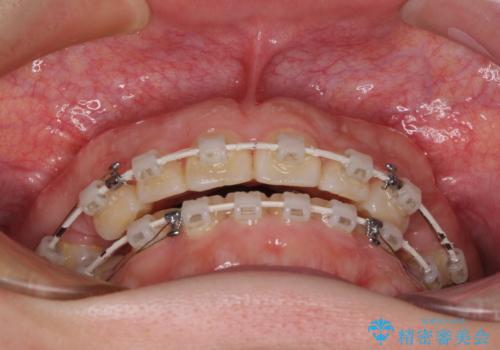

- 矯正装置

- 審美装置

- 2年6ヶ月

- 10-30回

口元の突出感を改善するため、上下左右第一小臼歯4本の抜歯を行い、ワイヤー装置による矯正治療を行うこととしました。